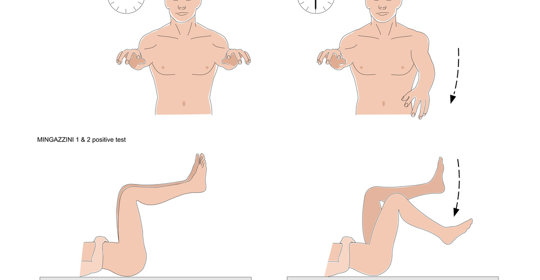

偏身萎縮:腓神經傷害的治療方法與垂足症的恢復

偏身萎縮:四種神經系統疾病的區別與治療